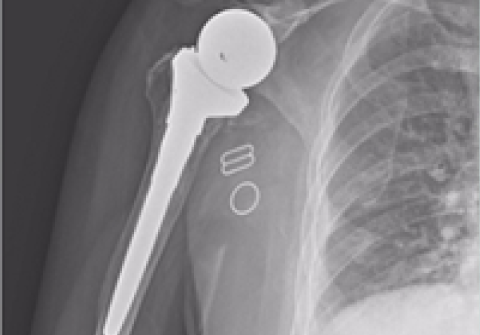

어깨 인공관절 역 전치환술

2013.10.05

2013.12.19

어깨 인공관절 부분치환술

2010.11.23

2011.03.17